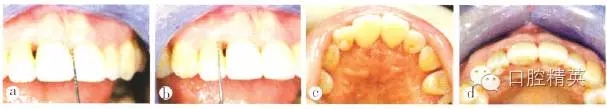

1.3.2效果追蹤

修復(fù)后2周復(fù)查,11間“黑三角”接近消失,鄰間隙關(guān)閉效果基本達到;到間唇側(cè)牙齦增厚,但仍有2~3 mm高的齦乳頭缺陷,繼續(xù)觀察其生長,并對患者進行定期牙周維護(圖8)。修復(fù)后1年復(fù)查,11間齦乳頭充盈良好,21間齦乳頭充盈程度改善,但尚未完全充滿,上前牙區(qū)唇側(cè)外形輪廓豐滿。患者微笑時,可見上前牙“黑三角”基本消失(圖9)。

a 11間“黑三角”接近消失;b 21間唇側(cè)牙齦增厚,但仍存在2-3mm高的齦乳頭缺陷;c 上前牙腭側(cè)觀;d 上前牙牙合面觀

圖8 修復(fù)后2周復(fù)查

a上前牙區(qū)正面觀,11間齦乳頭充盈良好,21間齦乳頭充盈程度改善,但尚未完全充滿;b上前牙區(qū)牙合面觀,唇側(cè)外形輪廓豐滿:c上前牙區(qū)腭側(cè)觀;d患者微笑像.“黑三角”基本消失;e上前牙區(qū)側(cè)面觀

圖9 修復(fù)后1年復(fù)查